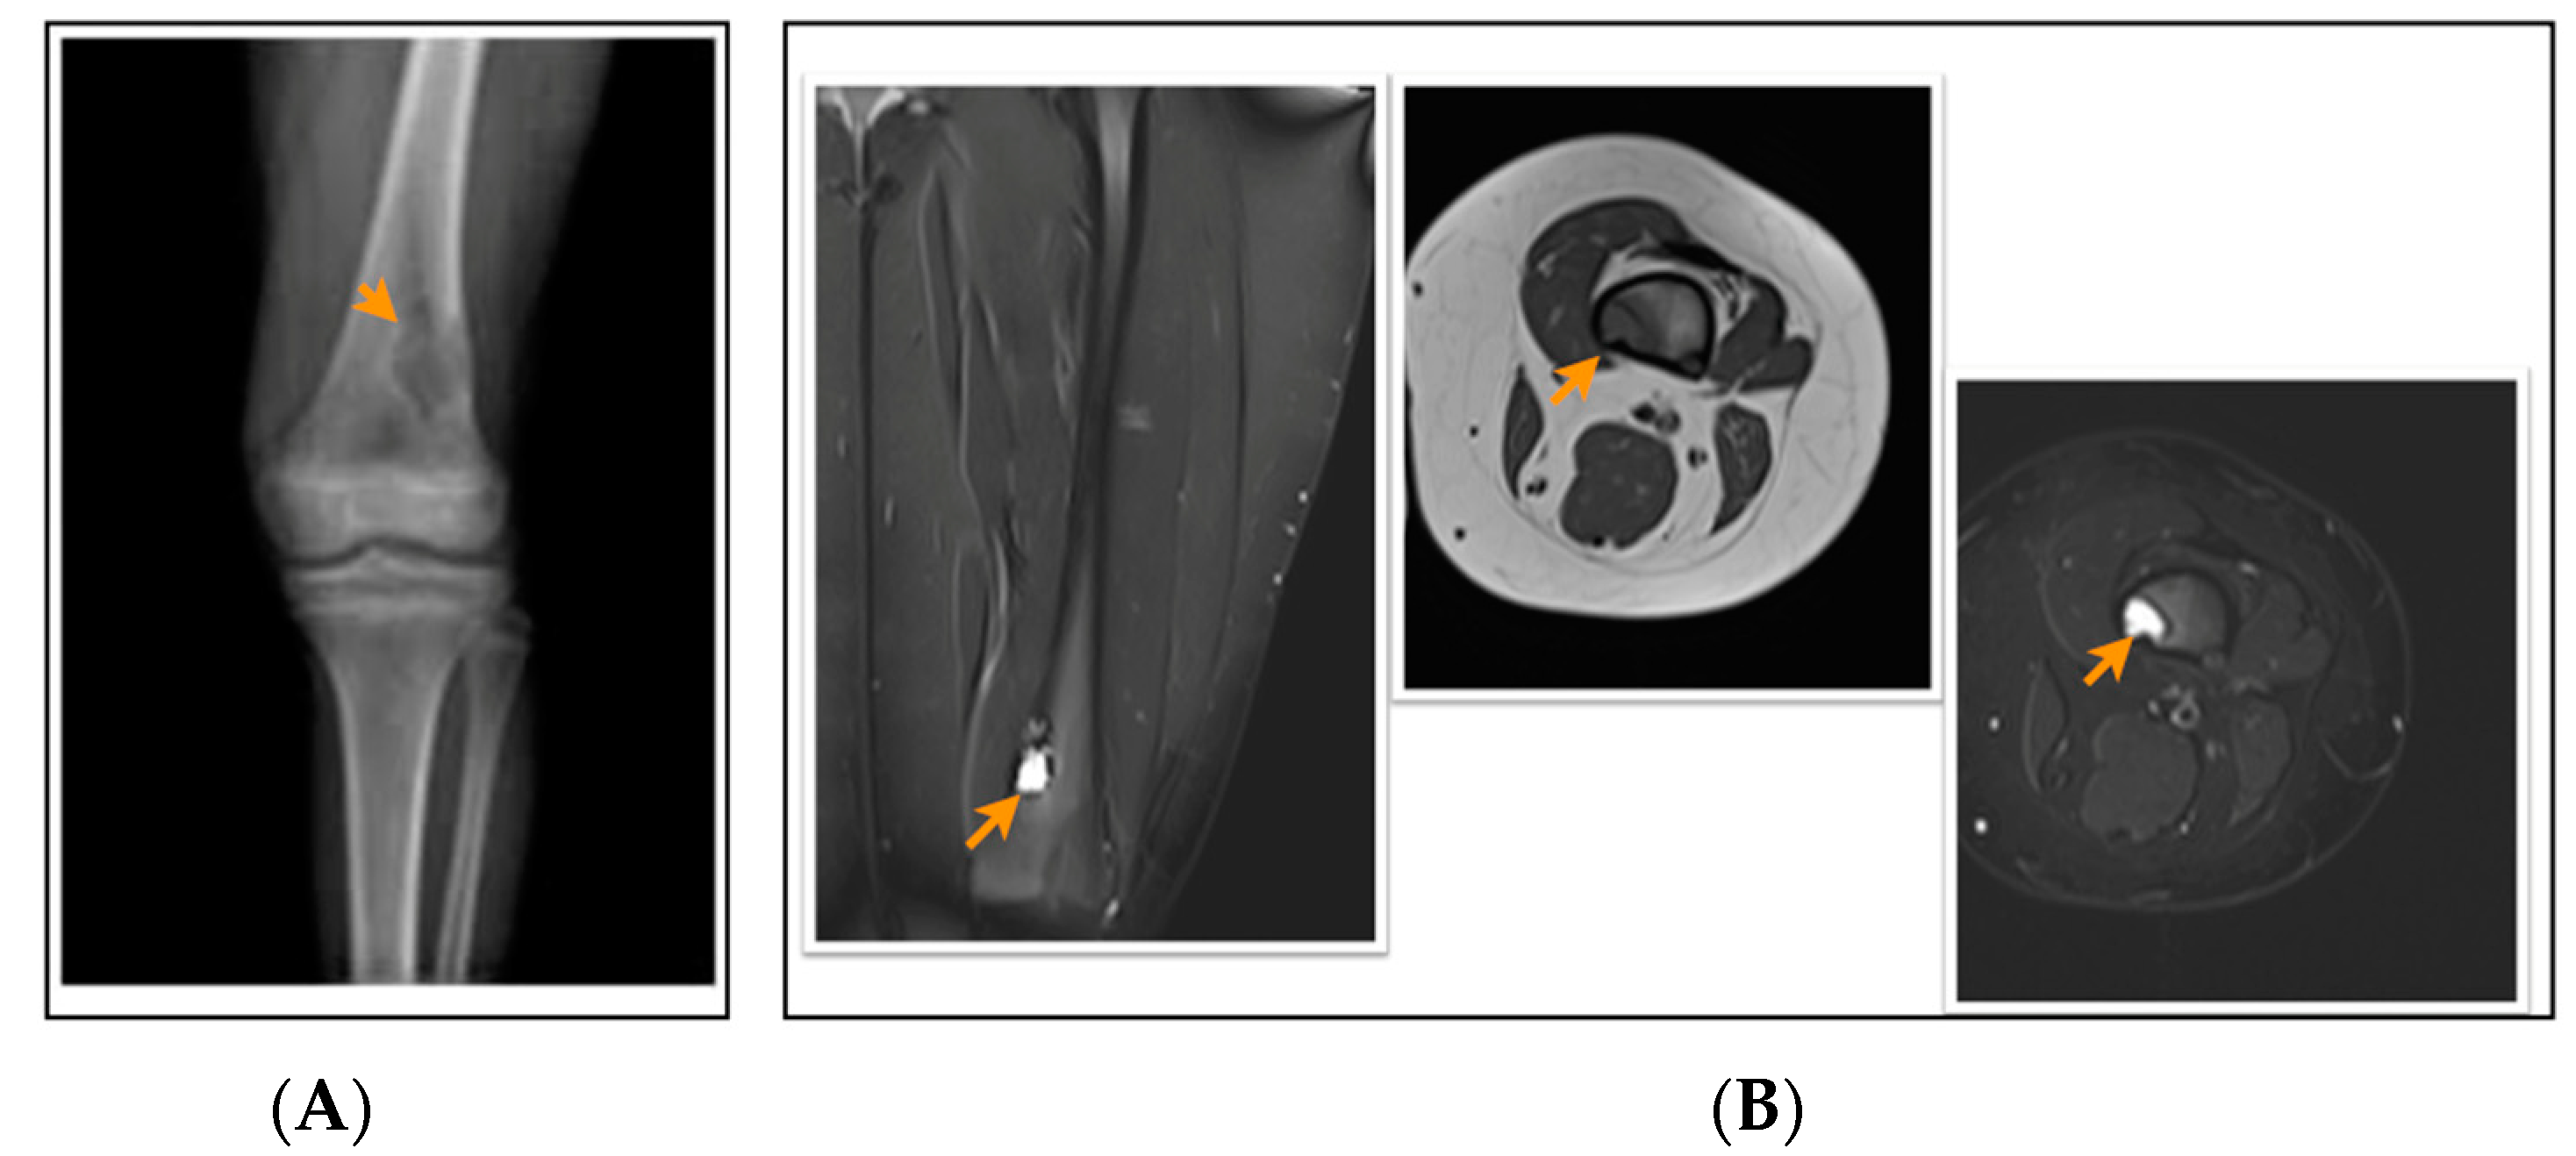

2.2. Radiological Evaluation of FCD/NOF